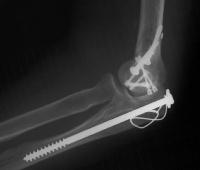

She began immediate protected motion and discontinued splint use at two weeks, despite recommendations to the contrary. These films are two months postop:

Lateral column not yet fully consolidated on Xray, but clinically healed.